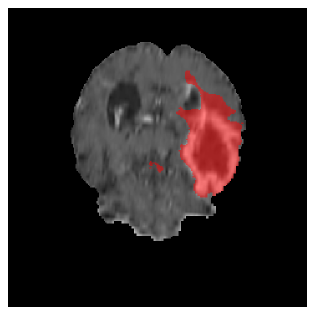

Appendix A Qualitative results

Figures 4 and 5 present the segmentation results for a patient from the BRATS dataset, visualized on a randomly selected slice. Figure 4 illustrates how tumor segmentation evolves over multiple episodes in S1 across different approaches including cumulative, naive, our approach, and the best buffer-free strategy (SI, =2). The cumulative approach, which trains on all encountered datasets together, maintains segmentation consistency across episodes but introduces significant amounts of false positives, particularly in the upper left area of the brain images. These misclassifications highlight its inability to generalize well across datasets despite access to all previous data. The naive approach, which learns sequentially without any continual learning strategy, suffers from severe catastrophic forgetting. While it initially segments well, performance deteriorates over episodes, leading to a near-complete loss of segmentation capability by the final episode. The SI (=2) approach, a regularization-based buffer-free CL strategy, performs reasonably well in early episodes but shows a significant performance decline over time. By the last episode, much of the tumor was no longer segmented, indicating difficulty in retaining prior knowledge. In contrast, our proposed approach initially produces more false positives but progressively refines its segmentation. By the final episode, it accurately retains the tumor region while minimizing misclassifications, demonstrating strong knowledge retention and adaptability across episodes. This suggests that our approach effectively mitigates catastrophic forgetting while maintaining segmentation performance over sequential learning.